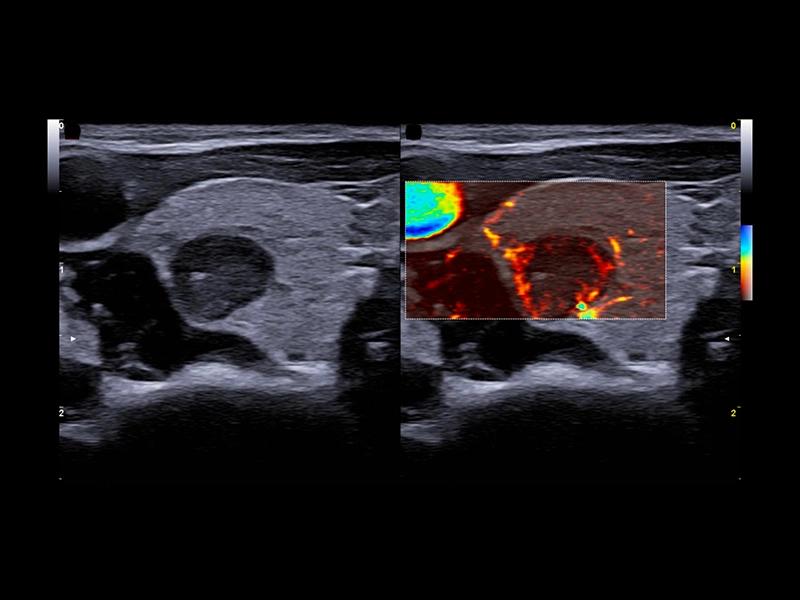

MyLab™9 Platform - Dual ElaXto characterization on breast lesion

MyLab™9 Platform - Dual ElaXto characterization on breast lesion